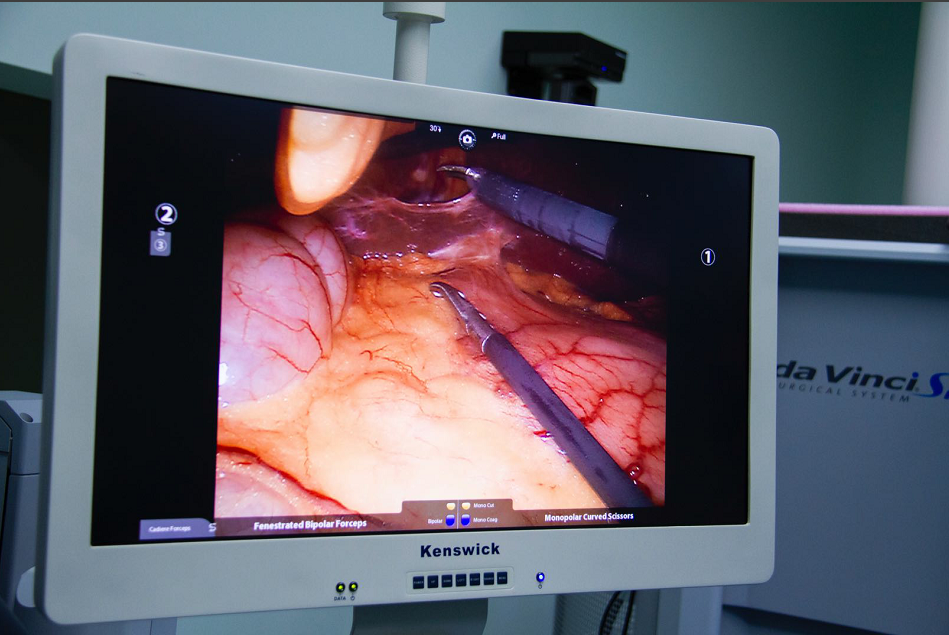

达芬奇手术机器人给患者手术中

1、机器人的摄像系统为外科医师提供了更清晰和逼真的三维视野,机器人的“眼睛”高清立体,手术视野放大10倍,细小的组织也难逃火眼金睛;

光学放大10倍的高清晰立体图像